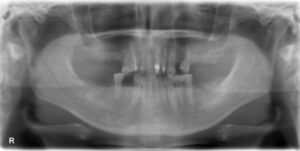

下顎臼歯3本欠損症例

BEFORE AFTER 61歳女性/下顎3本/インプラント埋込手術 【治療内容】 歯肉の腫れ、痛みが主訴でご来院の患者…